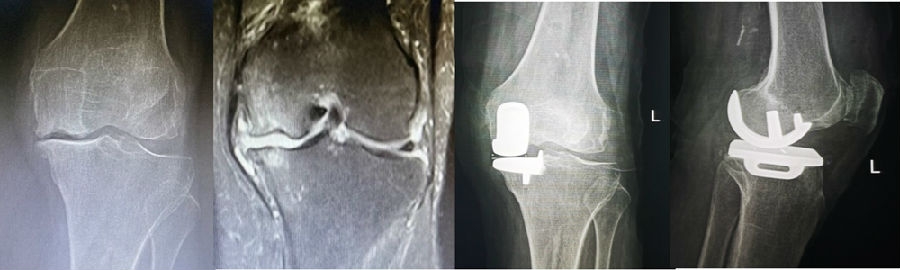

病例2:女,81岁,行内侧单髁手术治疗,术后恢复良好。